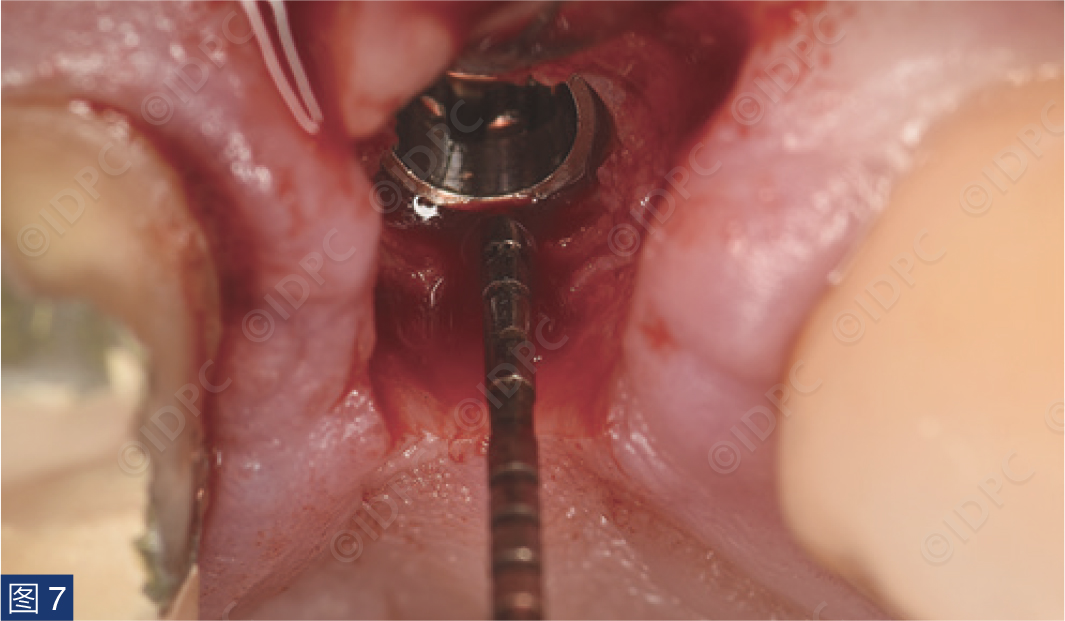

手术在局部麻醉(盐酸阿替卡因4% 1:100,000)下进行。行保留乳头的U形腭侧切口,翻全厚瓣并卷向颊侧(图5)。在皮瓣卷向颊侧的部分进行去上皮。这将弥补颊侧软组织缺损。逐级备洞,植入copaSKY 4 x 10种植体,植入扭矩30 Ncm(图6)。植体边缘放置在牙槽嵴顶下1 mm,以补偿未来牙槽嵴上方的软组织变宽(图7)。

图7:根据预期生物学宽度将种植体边缘置于牙槽嵴顶下方。